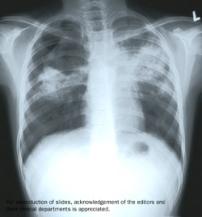

Tuberculosis is a chronic inflammatory disease whose damage to the body is mainly due to the type-IV hypersensitivity reaction provoked by the presence of Mycobacteria. Mycobacteria have the ability to enter into and survive inside macrophages, eventually causing these to lyse and a new cycle of infection to start. The immune system forms granulomas at the sites of infection, which can be seen in X-rays as distinct dense masses in the lungs. Activated macrophages are necessary to kill intracellular mycobacteria. Granulomas temporarily control the disease (latent TB) but the bacilli can reactivate later in life as immunity wanes (active TB). Multiple and extensive drug resistances in mycobacteria pose a very serious threat.